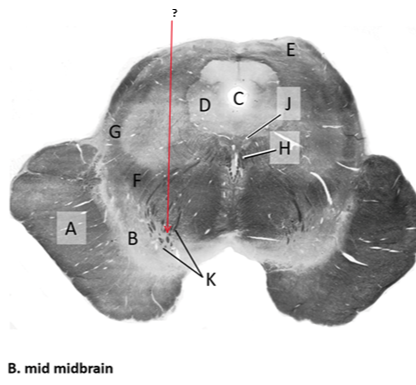

Name this and state its function.

Tectum.

Name this and its divisions+ function?

Substantia nigra.

Cerebral aqueduct.

Crus cerebri.

Medial Lemniscus.

Name this, what is it and state its function.

Lateral lemniscus.

Name this, state its function[2 marks] and how it goes about its function[4 marks].

Medial longitudinal lemniscus.

Oculomotor nucleus.

Name this, state its function[3 marks] and cells involved contributing to function.

Periaqueductal grey.

Root fibres of Oculomotor nerves(CN III).